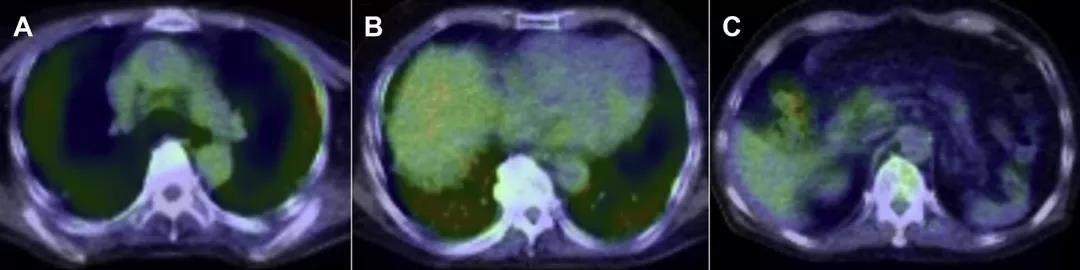

因CEA、CA199偏高怀疑腺癌可能,遂予全身检查,但腹部超声及CT未见异常。PET-CT示双肺外周FDG弥漫性摄取,而纵隔、肺门淋巴结、腹腔内器官与腹膜未见异常(图3)。

PET-CT用于排查恶性肿瘤,本例肺外周黏液栓显示为弥漫性FDG摄取,据Heyneman与Patz报道,局限性IMA的PET-CT检查FDG摄取常为假阴性,但其中6/7例(86%)的多灶性IMA表现为FDG弥漫性的摄取阳性。

所以在恶性肿瘤与间质性肺疾病并存时,肺PET-CT扫描也许难以作出诊断。